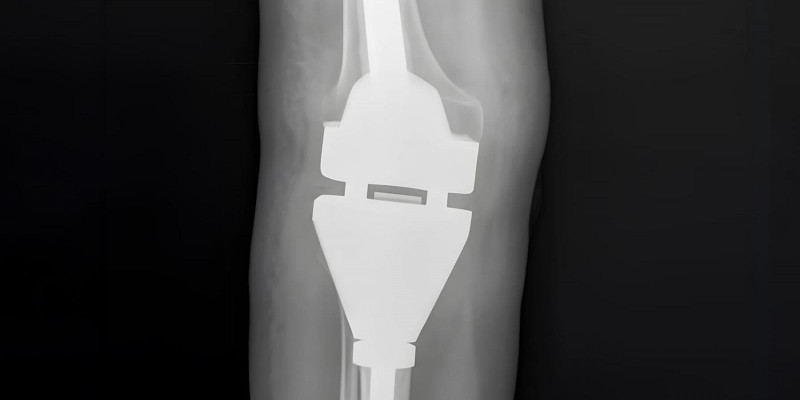

В Самаре впервые в России установили нераздвижной эндопротез коленного сустава, произведенный полностью из российских материалов в Самарском государственном медицинском университете Минздрава России (СамГМУ). Операцию выполнили в Самарском областном клиническом онкологическом диспансере (СОКОД). Благодаря конструкции эндопротеза, разработанной в НИИ бионики и персонифицированной медицины СамГМУ, пациентка сможет нормально ходить без ограничений. Разработка замещает импортные аналоги и способствует формированию технологического суверенитета в здравоохранении.

У 56-летней пациентки диагностировали гигантоклеточную опухоль верхней трети правой большеберцовой кости. Сначала врачи провели лекарственную терапию, а затем удалили опухоль, часть большеберцовой кости и установили на ее место эндопротез. Операцию выполняли руководитель Центра онкоортопедии, врач онколог-ортопед СОКОД, доцент кафедры травматологии, ортопедии и экстремальной хирургии им. академика РАН А.Ф. Краснова СамГМУ Виктор Иванов и директор НИИ бионики и персонифицированной медицины СамГМУ, врач онколог, д.м.н., доцент Андрей Николаенко. Особенность онкологического эндопротезирования в том, что после удаления опухоли эндопротезом необходимо заместить обширный участок. Операция длилась три часа и прошла без осложнений.

«Такая конструкция была впервые применена в Самарской области, – подчеркнул Виктор Иванов. - Благодаря этой конструкции мы не только сохранили ногу, радикально удалив опухоль, но и максимально сохранили функцию ноги, а значит и качество жизни пациентки. Сейчас она чувствует себя хорошо, уже может ходить, опираясь на ногу. После реабилитации она сможет вернуться к обычной жизни».